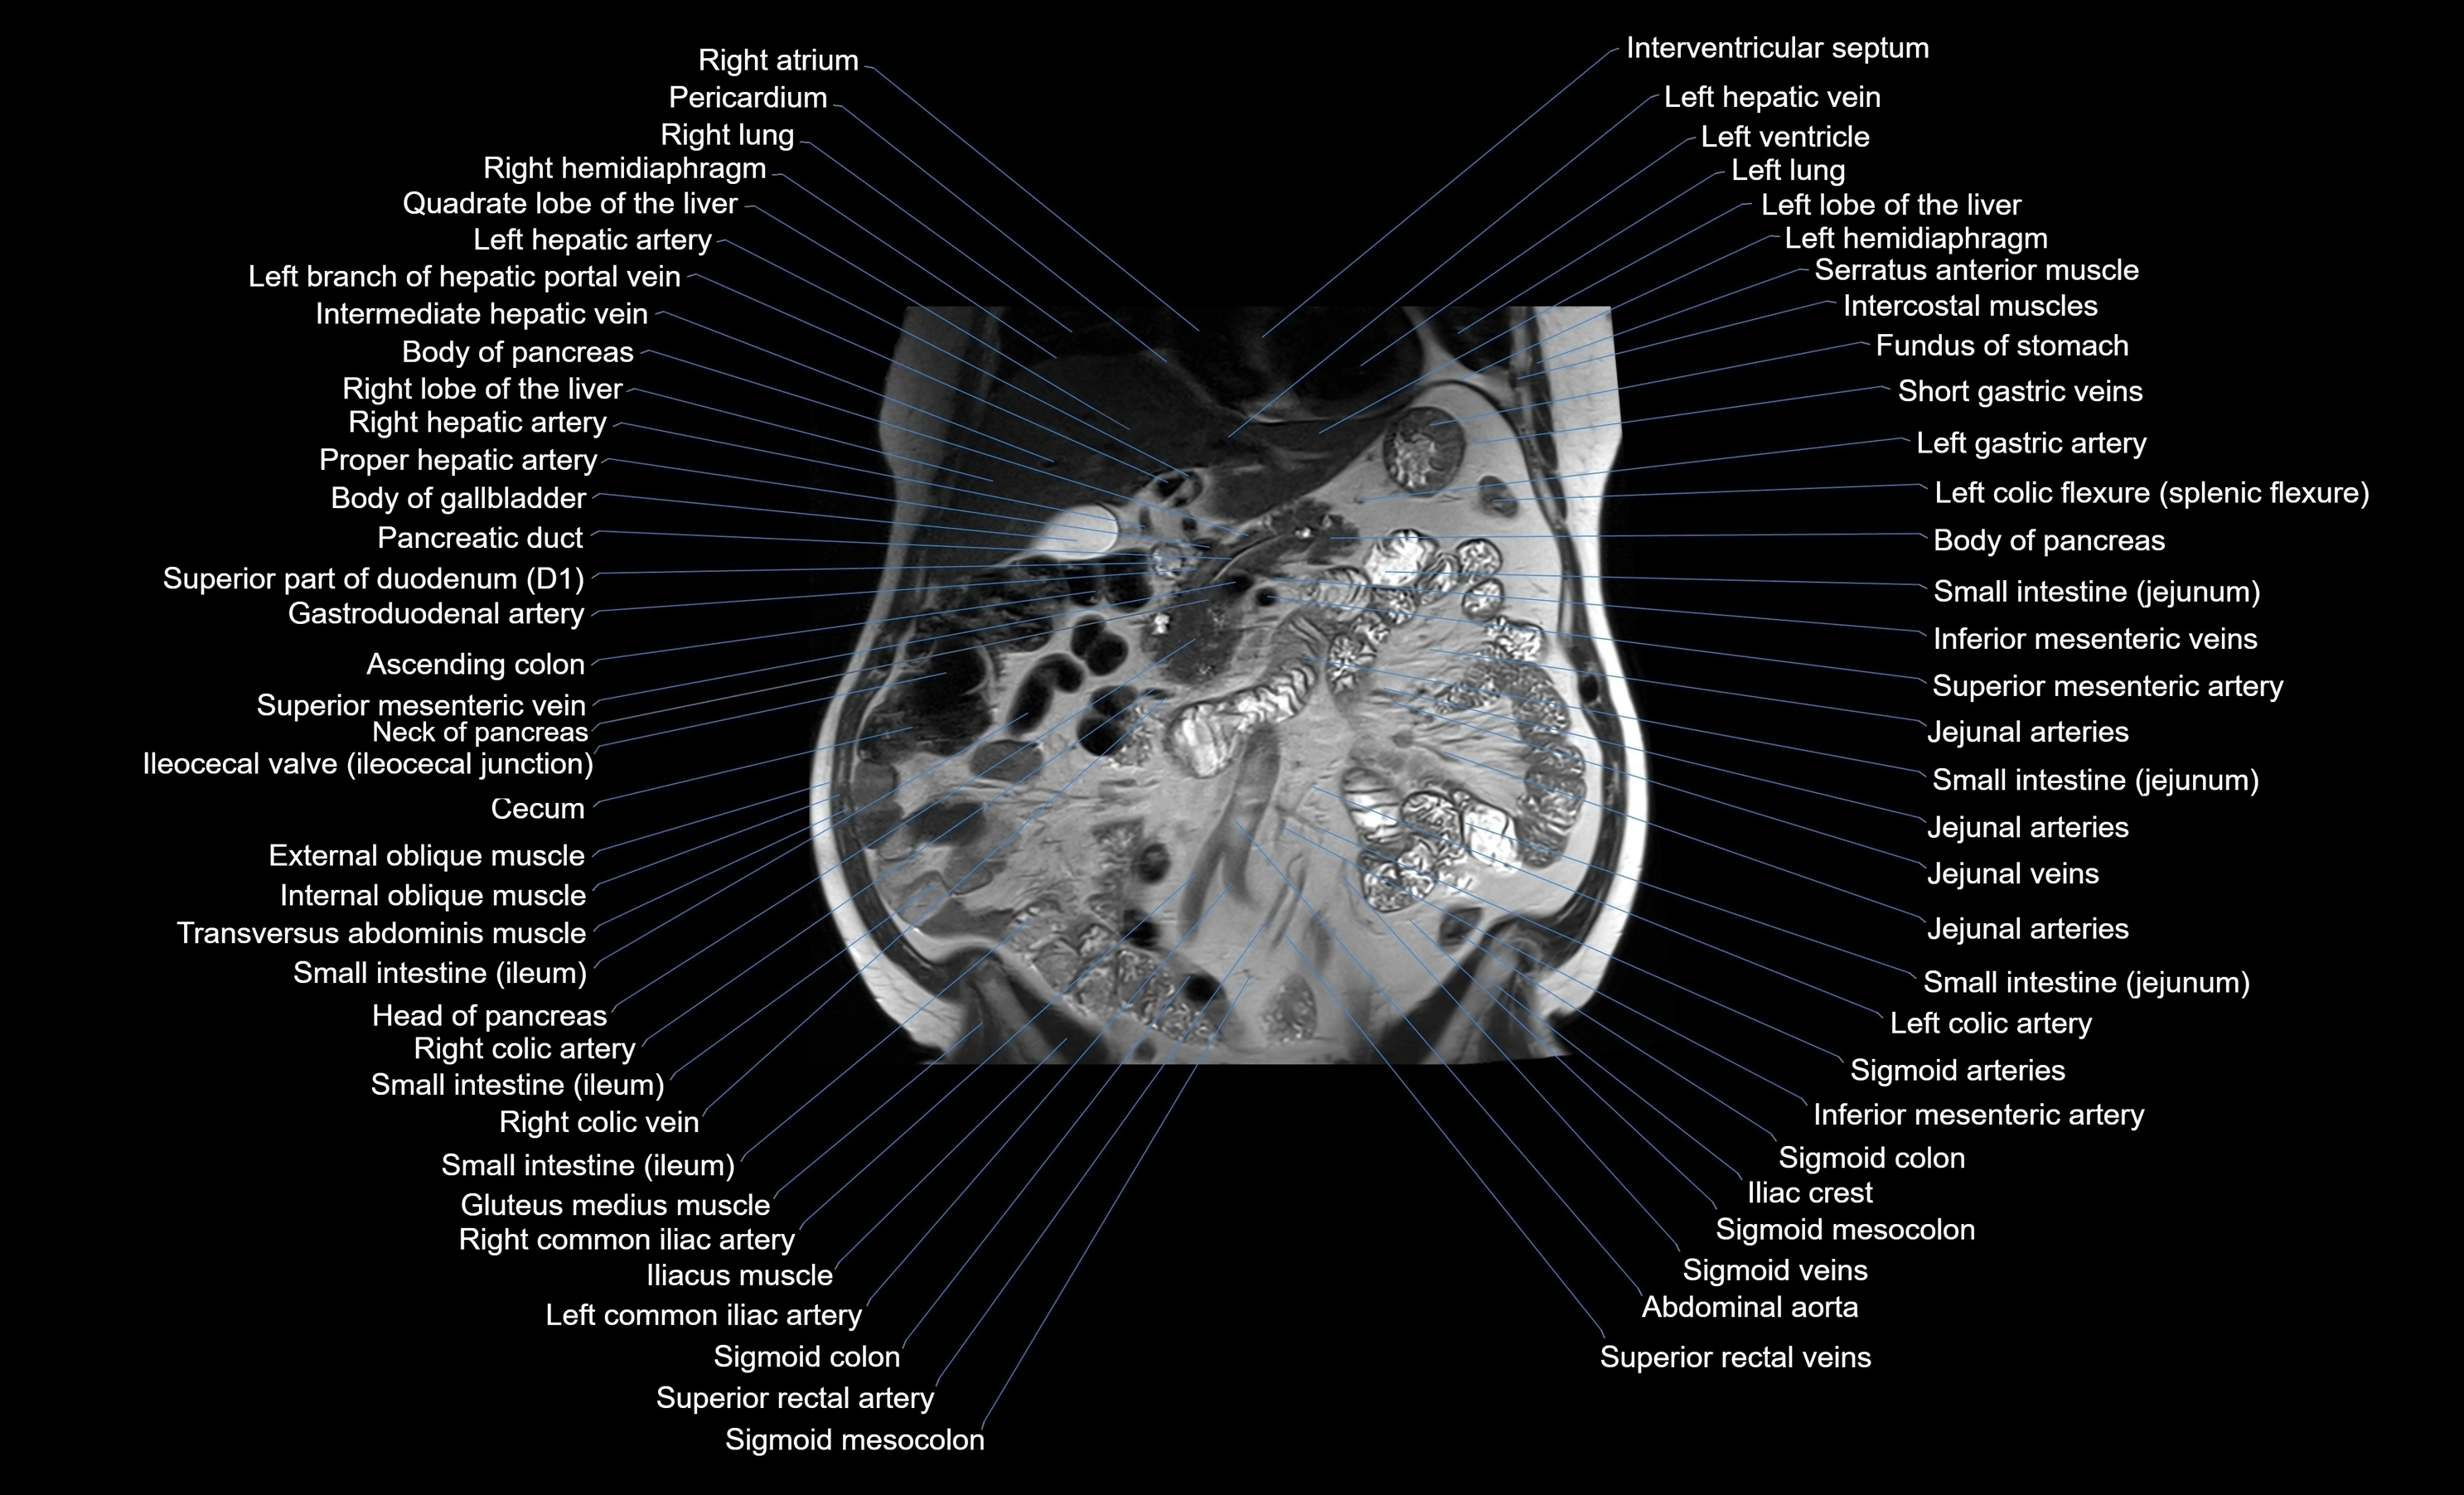

MRI images